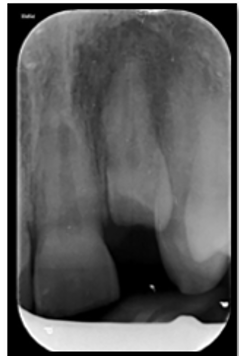

CBCT Imaging & Diagnostics

We are qualified to prescribe and review 3D CBCT imaging. This provides precise 3D views of root of teeth for accurate diagnosis and planning—minimising guesswork and improving outcomes.

- High-resolution 3D visualisation

- Targeted field of view to reduce exposure

- Improved detection of complex anatomy